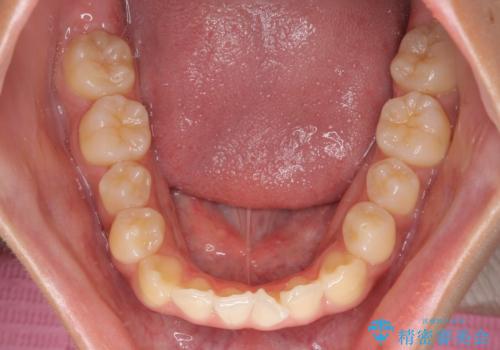

- 前歯の開咬と、受け口による咬み合わせの悪さを気にして来院された患者様です。

上顎歯列が狭窄していたため、急速拡大装置により上顎骨を側方に拡大し、その後ワイヤー装置にて矯正治療を行うこととしました。